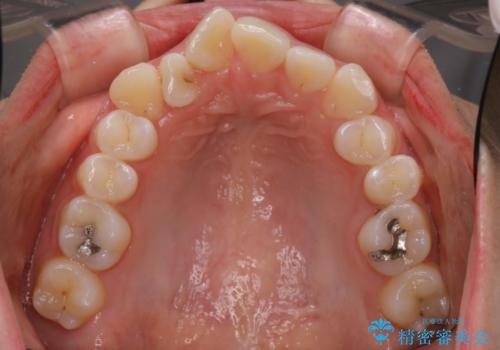

- 前歯のがたつきと出っ歯が気になるとのことで来院されました。

上顎の前から4番目の歯を両側合計2本抜歯して矯正することとなりました。